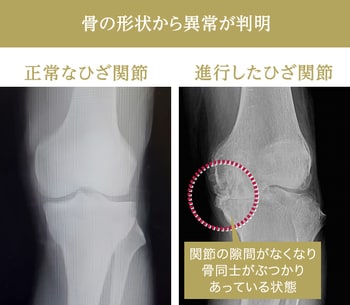

シンプルな写真情報なので骨の形状の変化がわかりやすく、骨や関節がどれくらい変形しているかが読み取れます。変形性膝関節症にはレントゲン写真から進行具合を診断する指標があり、関節の隙間の広さや骨の形によって、正常なひざから末期のひざまでをゼロ〜4までのグレードに分類することができます。グレード2の初期であればヒアルロン酸注射を行いつつ運動療法で経過をみることが多いでしょう。グレード3〜4くらい進行してしまっている場合は、手術を考えるようなひざの状態ということになります。